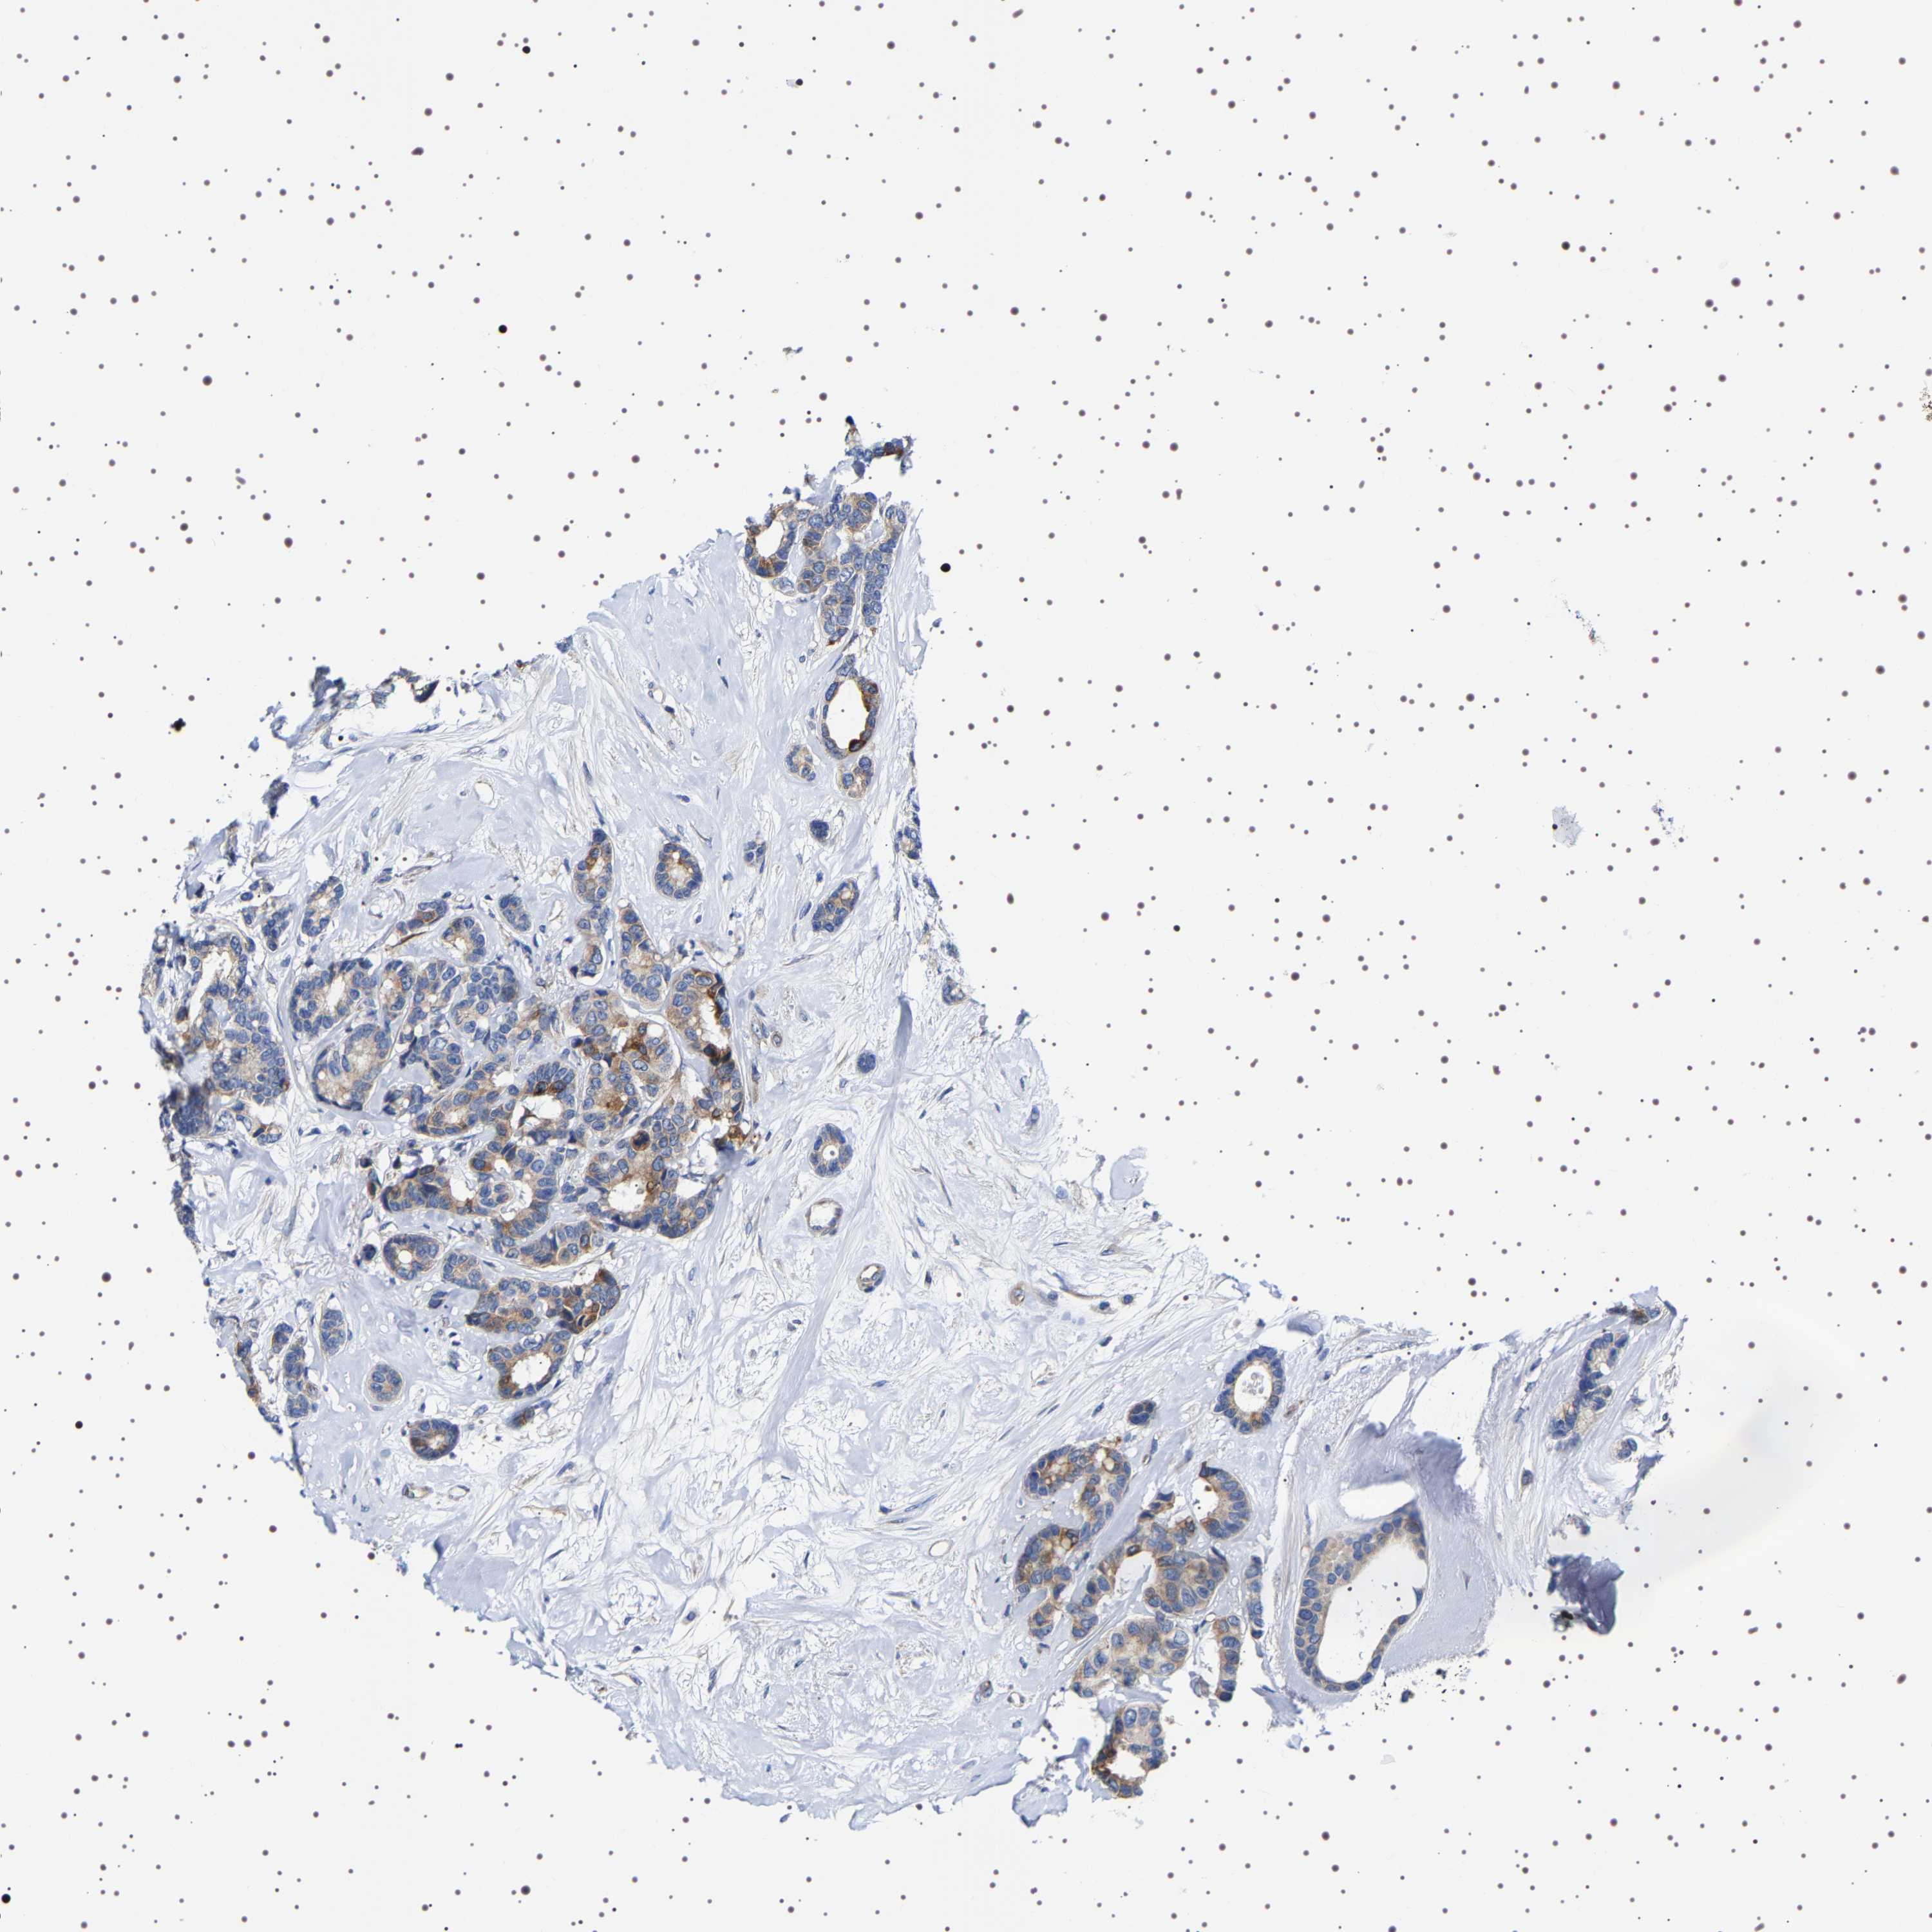

BRCA TCGA BRCA VALIDATION PROTEIN EXPRESSION